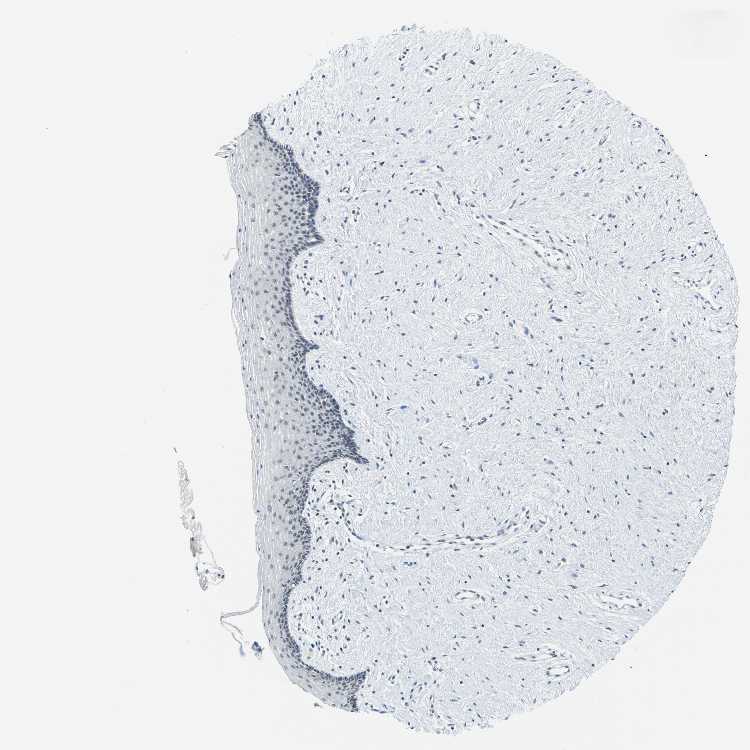

TISSUE PRIMARY DATA VAGINA Show tissue menu

VAGINA - Antibody stainingi

Antibody staining in the annotated cell types in the current human tissue is reported as not detected, low, medium, or high, based on conventional immunohistochemistry profiling in selected tissues. This score is based on the combination of the staining intensity and fraction of stained cells.

Each image is clickable and will lead to virtual microscopy that enables deeper exploration of all samples and also displays staining intensity scores, fraction scores and subcellular localization as well as patient and tissue information for each sample.

Antibody CAB017548

Squamous epithelial cells Not detected